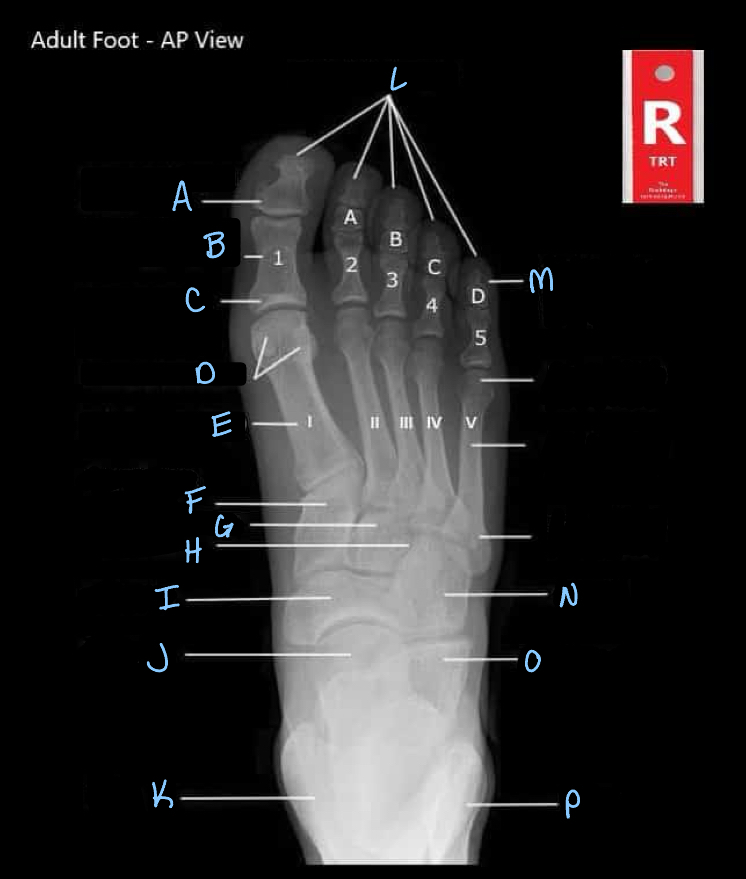

What is A?

interphalangeal joint

What is B?

proximal phalanges

What is C?

metatarsophalangeal joints

Q

sesamoid bones

medial cuneiform

intermediate cuneiform

lateral cuneiform

24

What is J?

What is K?

tibia

What is L?

distal phalanges

What is M?

intermediate phalanges

28

cuboid

What is O?

calcaneum

What is P?

fibula